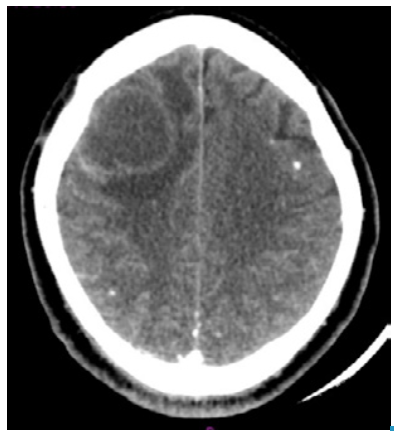

The neurology service requested a computed tomography (CT) that revealed a dilation of the supratentorial ventricular system and a right frontal subcortical cystic lesion that created a mass effect with midline shift. In addition, he presented perilesional edema and small residual bilateral frontoparietal calcifications, suggesting sequelae of NCC (Figure 1). Blood count, C-reactive protein (CRP) and renal function were normal. Pharmacological management was initiated with albendazole at an oral dose of 1600mg every 24 hours, dexamethasone 8mg IV every 8 hours, paracetamol at an oral dose of 1g every 8 hours and omeprazole at an oral dose of 20mg every 24 hours. The patient did not report any side effect caused by these drugs.

Computed tomography with right frontal subcortical cystic lesion, perilesional edema and calcified nodules.

Figure 1: Computed tomography with right frontal subcortical cystic lesion, perilesional edema and calcified nodules.

Source: Own elaboration based on the data obtained in the study.